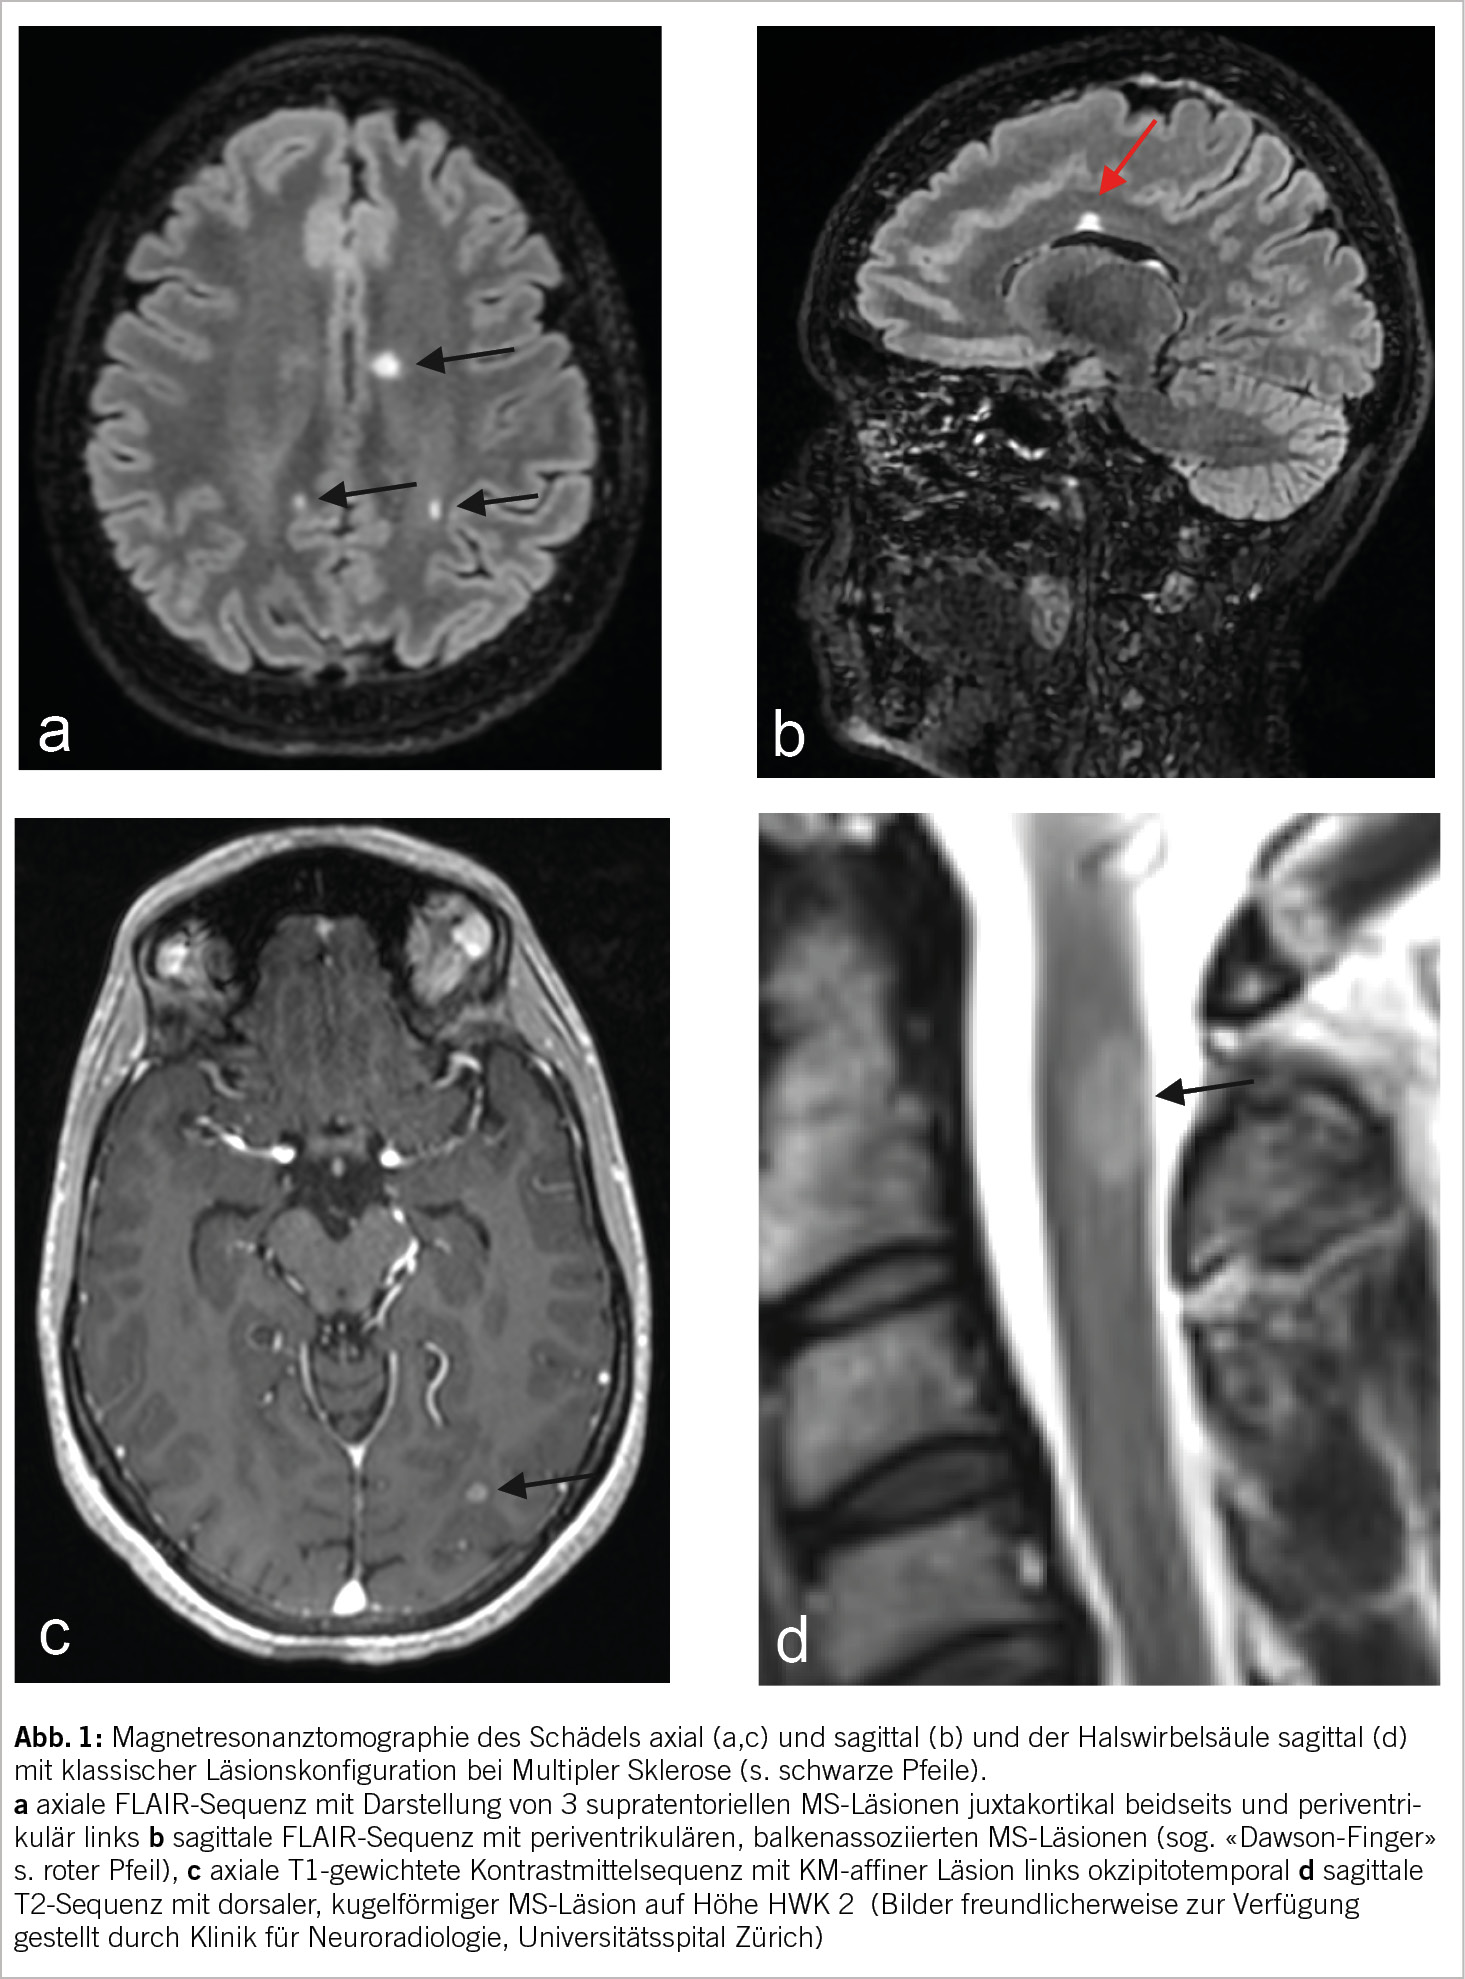

Im ersten Schritt sollte im Anschluss an eine detaillierte Anamnese und klinisch-neurologische Untersuchung bei anhaltendem Verdacht ein MRI mit Kontrastmittel des Schädels beziehungsweise, je nach Symptomatik, des Rückenmarks mit der Frage nach chronisch-entzündlichen Veränderungen erfolgen. Die vier klassischen Lokalisationen der meist oval, relativ scharf begrenzten, später konfluierenden MS-Läsionen sind juxtakortikal, periventrikulär, infratentoriell und spinal (siehe Abbildung 1). Aktive entzündliche Läsionen zeichnen sich durch ihre Kontrastmittelaufnahme aus (4).